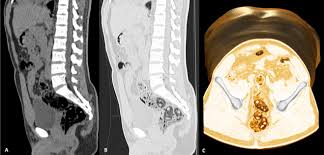

Ct Images Of Two Patients With Either Water Only Or Telebrix Gastro As Download Scientific Diagram